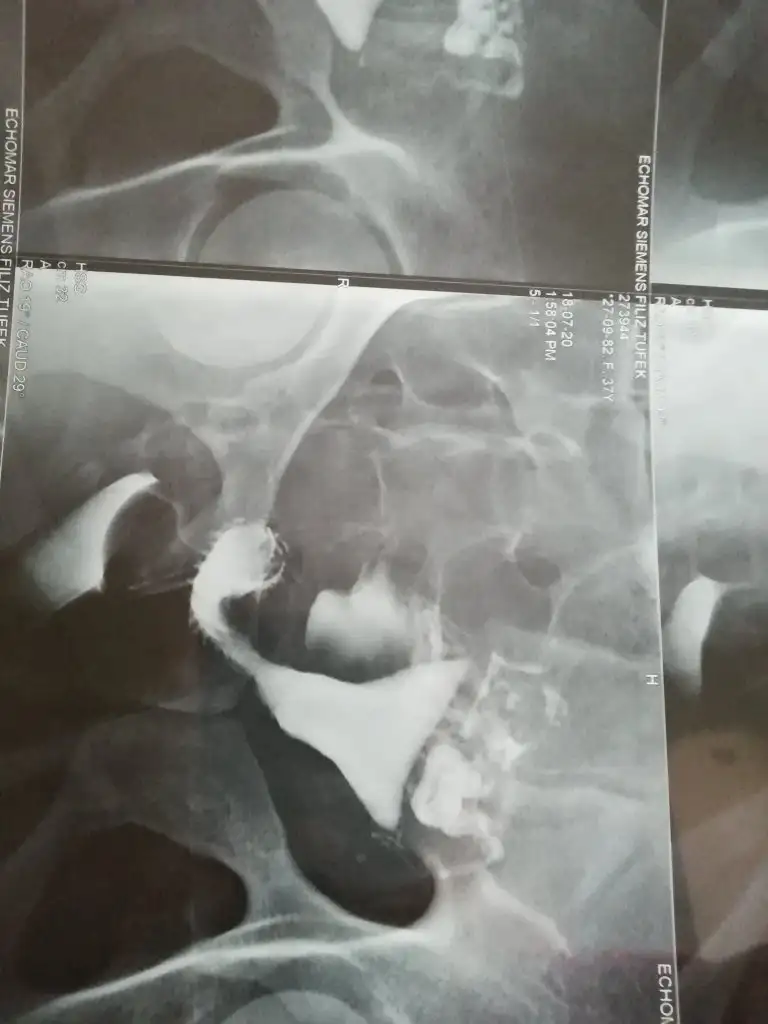

Rahim filmi arkadaslar anlayan var mi?

Kizlar dun rahim filmi cektim anlayan varsa yorum yapabilir mi lutfen?

Rapor yazması lazım orda daha net bilirdik ne olduğunu. Bak ben sana örnek kendi filmimi göndereyim. Ve rahim şeklide öyle olması gerekiyormuş. Ve benim her iki tüpüm kapalıydı gördüğün gibi sadece 3 gen duruyor

ben istanbula gittim canım orda özel bir merkez vardı orda açıldı çok şükür tavsiye ederim. senin filminden bişey anlamadım desem yeridir çok farklı garip duruyor çünki. benim filmi incelersen anlarsın zaten seninkinin değişik olduğunu

Merhaba bende bugün cektirdim sizin görüntünüzü anlayamadım benim ki çok net belli oluyor sağ tupum kapalı ☹️ açılmadı kapalı pldugu icin işlem sırasında sancım oldu ama dayandım mecburen . Bilginiz var ise birşey sormak istiyorum aşılama yaptirmayi planlıyorduk tek tüp ile tutma ihtimali nedir

Kızlar merhaba, bende rahim filmi çekildim baştan söyliyeyim anestezi ile oldum hiç birşey anlamadım. Uyandığımda ufak bir kanamam vardı oda normaldi ve yarm saat uyanık kalsam da o kısım kötüydü midem bulandı uyumamam gerekiyormuş yarım saat sonra tamamen kendime geldim. Antibiyotik ve ağrı kesici verdiler. Antibiyotik süresince ilişki yasağı koydular. Rahim filmime göre sağ tüpümün tıkalı olduğunu ve ameliyat olmam gerektiğini söylediler. Peşinden normal yolla da kalabilirsin dediler. Ameliyattan korkuyorum açıkçası çünkü görüp eğer açılmaZsa ameliyatta tüpü alacaklarını söylediler. Raporum bu sizce normal yolla hamilelik yaşayan var mı ?